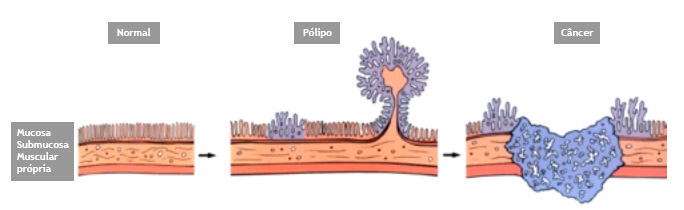

Colonoscopia é o exame endoscópico do cólon (intestino grosso) e muitas vezes também do íleo terminal (porção final do intestino delgado). Além da inspeção da superfície intestinal, a colonoscopia permite também a realização de biópsias que podem ser úteis no estabelecimento do diagnóstico. Procedimentos terapêuticos também podem ser realizados durante a colonoscopia, entre eles o mais frequente é a remoção de pólipos (polipectomia).

- Prevenção e detecção precoce do câncer de cólon. A colonoscopia pode ajudar a encontrar pólipos, que podem se tornar câncer. Os pólipos podem ser removidos através de polipectomia. O exame também pode permitir que seu médico encontre tumores cancerosos precocemente, quando é mais fácil de ser curado.

O que são pólipos?

Pólipos são crescimentos na parede interna do tubo digestivo em órgãos como o esôfago, estômago, duodeno e cólon. O cólon e o reto são partes do intestino grosso.

Por que devem ser removidos?

Se não forem removidos cedo, alguns pólipos podem se tornar cancerosos. Se pólipos cancerosos não são tratados, eles são uma ameaça à vida. Porém mesmo sendo canceroso, se for ressecado precocemente e se este não estiver muito infiltrado, a simples retirada do pólipo pode resolver o problema.

Geralmente apenas uma região do pólipo é que se apresenta de forma cancerosa. Se for realizada uma simples biópsia do pólipo, a região cancerosa pode não ser atingida e o diagnóstico de câncer não ser realizado. Para se ter certeza do diagnóstico, o pólipo inteiro deve ser removido através do procedimento chamado de polipectomia.

O que é a polipectomia?

A polipectomia é a remoção completa de um pólipo permitindo assim o diagnóstico exato e muitas vezes a cura do próprio problema. Existem várias técnicas para a realização do procedimento que dependem do tamanho e do tipo de pólipo a ser ressecado.